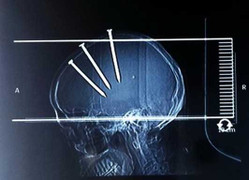

(VTC News) - Một người đàn ông đã nhập viện khẩn cấp sau khi được cho là tự bắn 3 cây đinh sắt vào đầu.